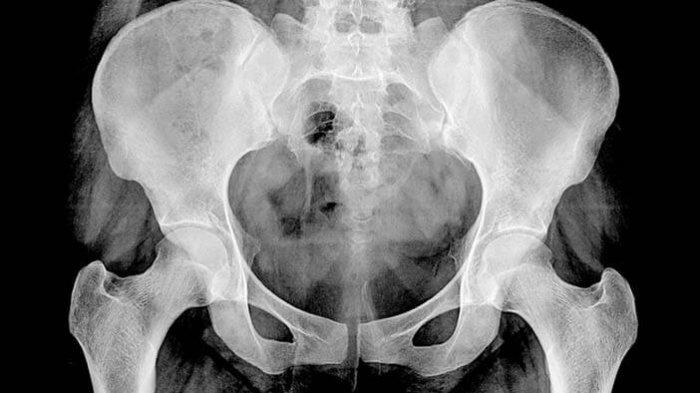

TRIBUNNEWSWIKI.COM - Avascular necrosis merupakan suatu kondisi ketika terdapat jaringan tulang mati karena kurangnya pasokan darah, sehingga menyebabkan kerusakan tulang, bahkan kehancuran tulang.

Avascular necrosis dapat disebut juga sebagai osteonecrosis, aseptic necrosis, atau ischemic bone necrosis.

Avascular necrosis terjadi akibat kurangnya pasokan darah ke tulang